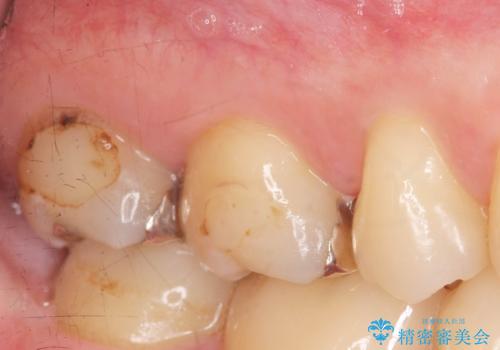

メタルフリー治療 銀歯を全て除去したい

- 口腔内の金属、銀歯を全て除去しセラミックにしたい。と、希望され来院されました。

口腔内の金属を丁寧に除去したのち、精度・審美性に優れるセラミック治療を計画します。